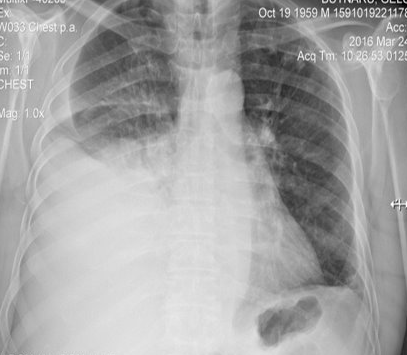

Rx toracică, incidență P-A

DESCRIERE:

DX: atelectazie prin NBP central endobronșic (pe bronhia principală stg)

DD: pleurezie masivă → caracter expansiv

la niv. întregului hemitorace stg → opacitate extinsă, nesistematizată, de intensitate mare, omogenă

caracter retractil → tracționează traheea și mediastinul de partea afectată

fără bronhogramă aerică

duce la micșorarea spațiilor intercostale

la niv. hemitoracelui controlateral → hipertransparență compensatorie (emfizem)